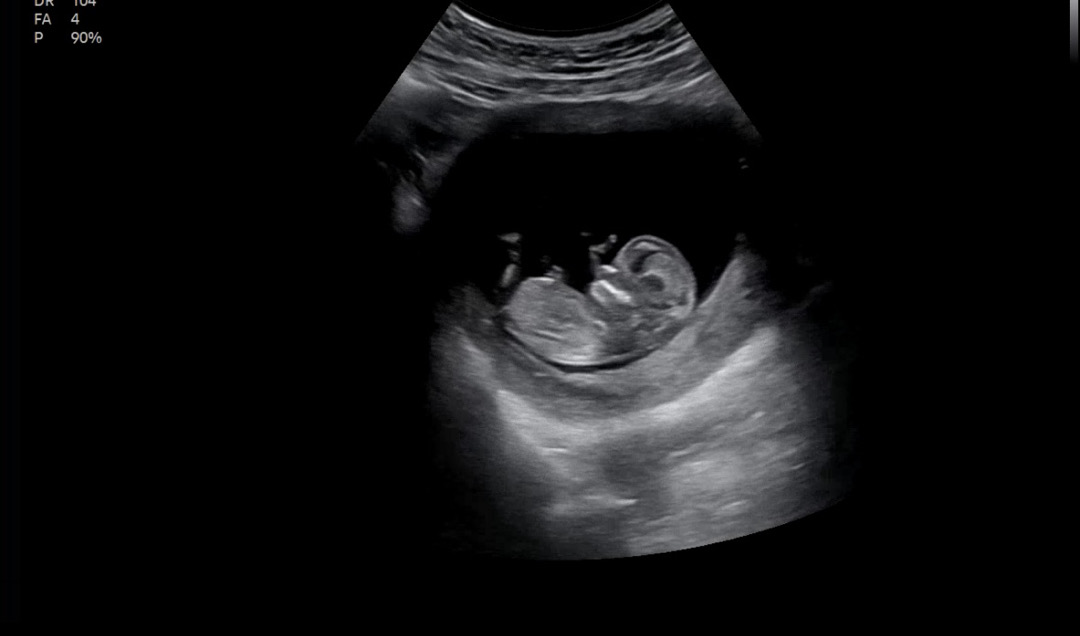

12주차 각도법 부탁드려요!!

니프티 했는데 넘넘 궁금해요! 각도법 고수님들 부탁드려요